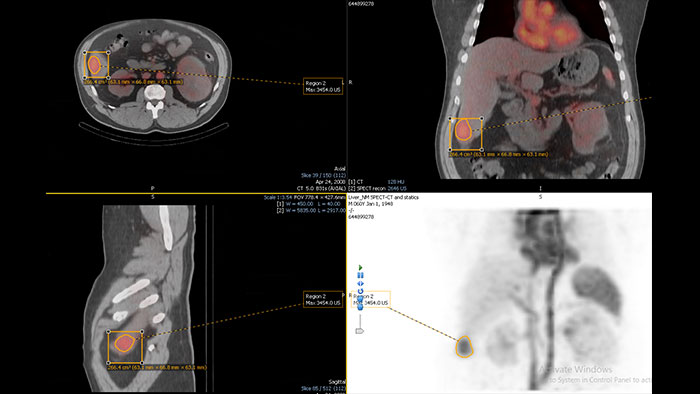

Streamlined workflow for follow up and analysis of oncology patients

MMTT is a post processing software used to display, process, analyze and quantify anatomical and functional images, for CT, MR, PET/CT, SPECT/CT and Dual Energy CT at one or multiple time points.

Benefits

Enhanced user experience for NM reading with a leading NM viewing solution

A comprehensive NM solution, designed to enhance productivity of PET/CT and NM reading. It offers a solution for handling multiple studies requiring rigorous quantification of MV data**.